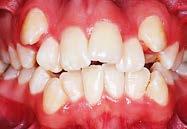

Se presenta una paciente clase ll esquelética en los estudios extrao rales en la fotografía de frente se ve hiperdivergente con una mordi da profunda de 5mm, un diastema, y refiere como motivo de consulta "no me gusta el espacio entre mis dien tes" (Figura 1).

En los estudios intraorales de inicio en las fotografías se muestra en la de frente el diastema anterior, con la línea media dental superior e inferior no coincidentes, la mordida profun da anterior (Figura 2), en la lateral derecha clase l molar y canina bila teral (Figura 3), el apiñamiento leve superior e inferior y la forma de las arcadas.

Figura 1. Extraoral de inicio de frente. Figura 2. Intraoral de frente derecha, izquierda. Figura 3. Oclusal superior e inferior arcadas cuadrada. Figura 4. Radiografía lateral de cráneo. Figura 5. Rx Panorámica.